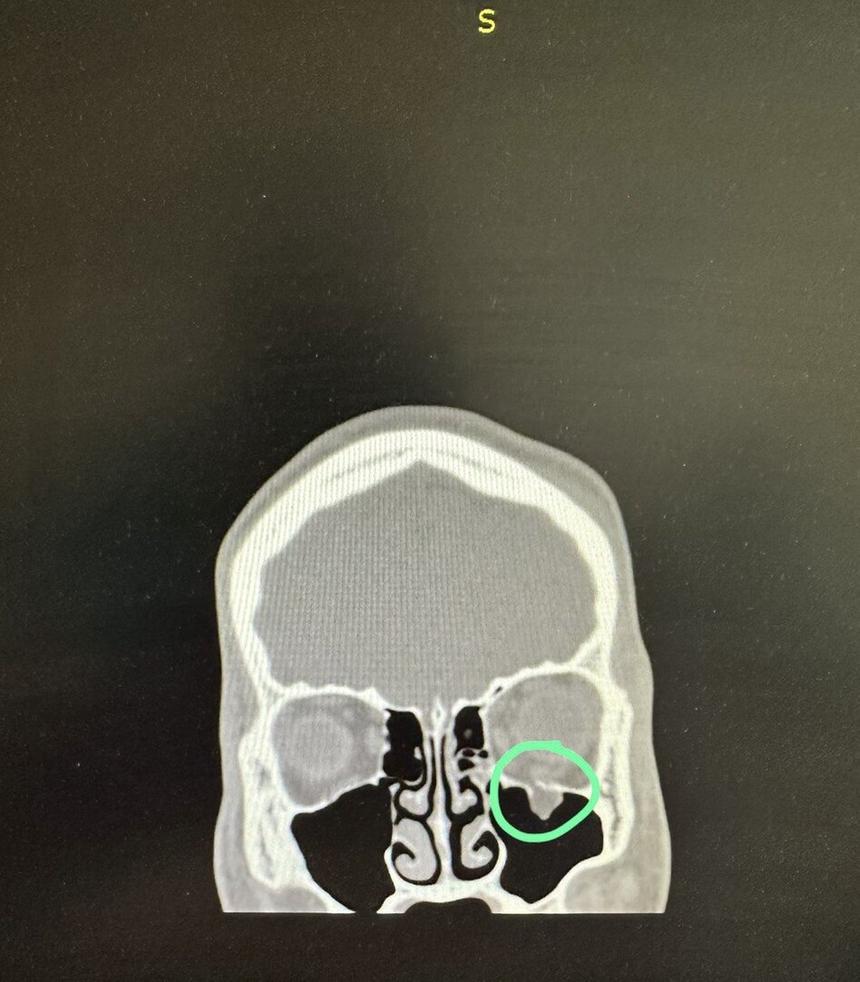

Мария поделилась, что лично искала свидетелей, писала ходатайства, и в итоге ей удалось добиться возбуждения уголовного дела по статье 213 УК РФ «Хулиганство». Но позже его переквалифицировали по статье 111 УК РФ «Умышленное причинение тяжкого вреда здоровью», так как была проведена медицинская экспертиза, доказавшая неизгладимость травмы — веко у пострадавшего опустилось и появилось двоение в глазах. Мама студента отметила, что он перенес две операции по имплантации дна глазной орбиты, но его зрение до конца не восстановлено.

Рентгеновский снимок пострадавшего после избиения

© Снимок предоставлен героиней публикации